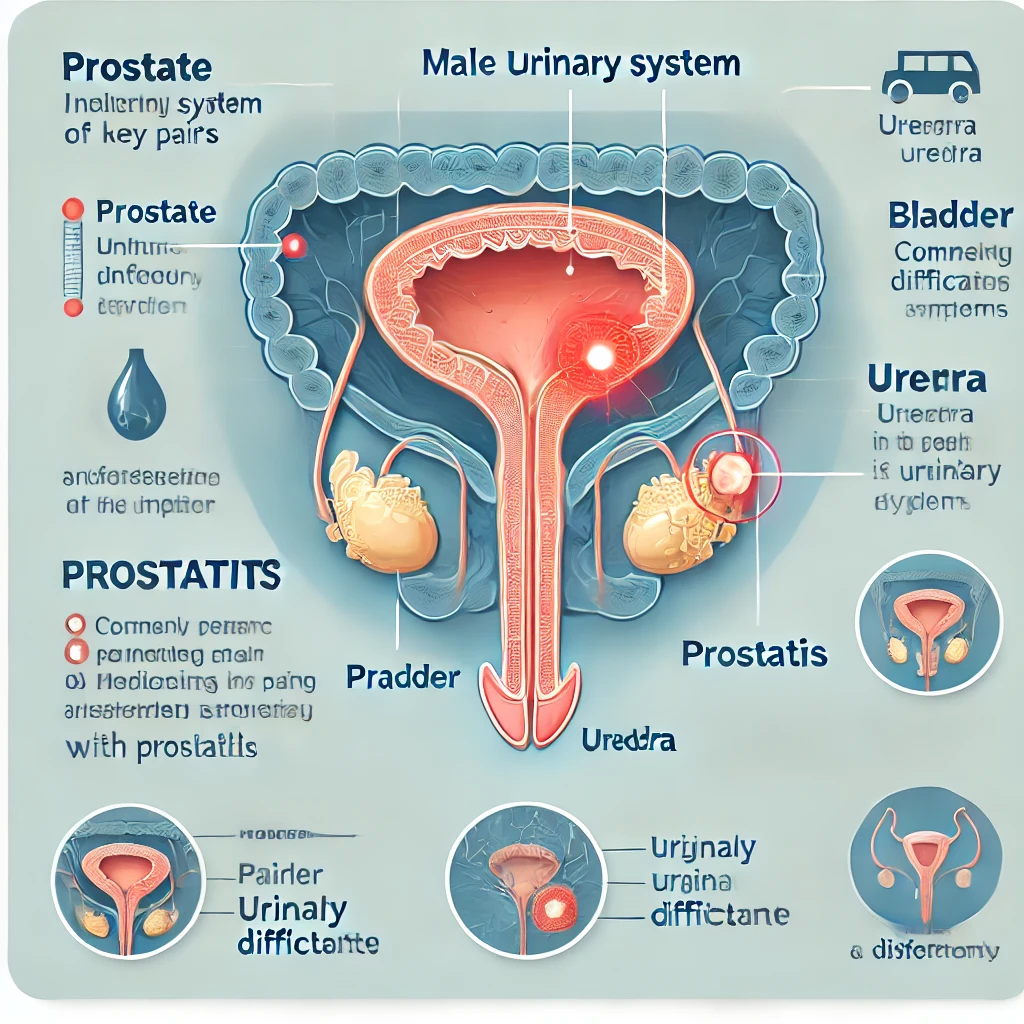

Prostata (neboli mužská prostata) se nachází pod spodní částí močového měchýře mezi stydkou kostí a konečníkem. Prostatická část močové trubice prochází tkání prostaty. U dospělého muže je hmotnost prostaty 15-28 gramů; u dětí je velikost prostaty velmi malá.

Vzhledem k obrovskému vlivu prostaty na fungování pohlavního systému a celého mužského těla se o ní často hovoří jako o druhém srdci muže.

Prostatitida je společný název pro skupinu zánětlivých onemocnění prostaty (prostaty). Chronická forma může po léta probíhat nepozorovaně, bez výrazných příznaků, ale může mít negativní dopad na kvalitu života muže. Často je prostatitida příčinou sexuologických poruch.

Existují dvě skupiny příčin problémů s prostatou: infekce a přetížení. Infekční prostatitida může být způsobena různými bakteriemi, viry nebo plísněmi. Nejčastějšími původci jsou nespecifické mikroorganismy: stafylokoky, streptokoky, Escherichia coli, Proteus, o něco méně často specifické mikroorganismy: gonokoky, trichomonády a další. V poslední době se zvyšuje počet chlamydiových, mykoplazmových aj. prostatitid.

Kongestivní (městnavá) prostatitida je způsobena stagnací sekretu v prostatě a/nebo krve v žilách tohoto orgánu, což se nejčastěji vyskytuje v následujících případech:

Stagnující prostatitida se v důsledku infekce velmi rychle změní v bakteriální prostatitidu. Je známo, že v mnoha případech prostatitidě předchází nebo ji doprovází zánět prostaty v močové trubici (uretritida).